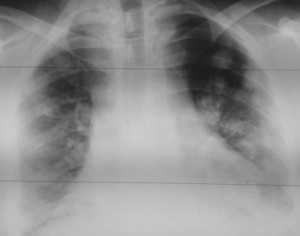

Как выглядят метастазы в легких на рентгене? Слева — узловые образования у пациента с раком яичка. Справа - метастазы рака яичников гематогенного характера с выраженным опухолевым лимфангиитом (обратите внимание на деформированный сетчатый, линейный характер легочного рисунка).

Слева - рак почки с метастазами в легкие, прогноз в данном случае неблагоприятный ввиду метастатического плеврита и дыхательной недостаточности. Определяются очаги с обеих сторон. Справа - мелко- и среднеочаговая диссеминация при раке печени.

Множественные гематогенные вторичные узлы при раке почки, компьютерная томография (КТ).

Лимфогенные метастазы на рентгене и КТ выглядят как множественные мелкие очаги с диссеминированным распространением, локализованные в междольковых перегородках, в плевральных листках. Вокруг можно видеть характерную картину ракового лимфангиита. Кроме того, практически всегда выявляются патологически измененные и увеличенные лимфатические узлы средостения. Лимфогенное метастазирование необходимо дифференцировать с милиарным туберкулезом, саркоидозом. Иногда это требует привлечения Второго мнения.

Лимфогенные метастазы проявляются увеличением лимфатических узлов средостения в сочетании с мелкоочаговой диссеминацией с очагами до 2-3 мм в диаметре вблизи плевры и в междольковых перегородках, а также по ходу бронхов и сосудистых пучков.

Гематогенные метастазы саркомы мягких тканей бедра на КТ (справа) и рентгенограмме (слева).

Обратите внимание на увеличение и нарушение структуры корня правого легкого. Это центральный рак. Кроме того, выявлены очаговые тени в обоих легочных полях (гематогенное распространение), а также «лучи», идущие радиально от опухоли корня (лимфогенное распространение).